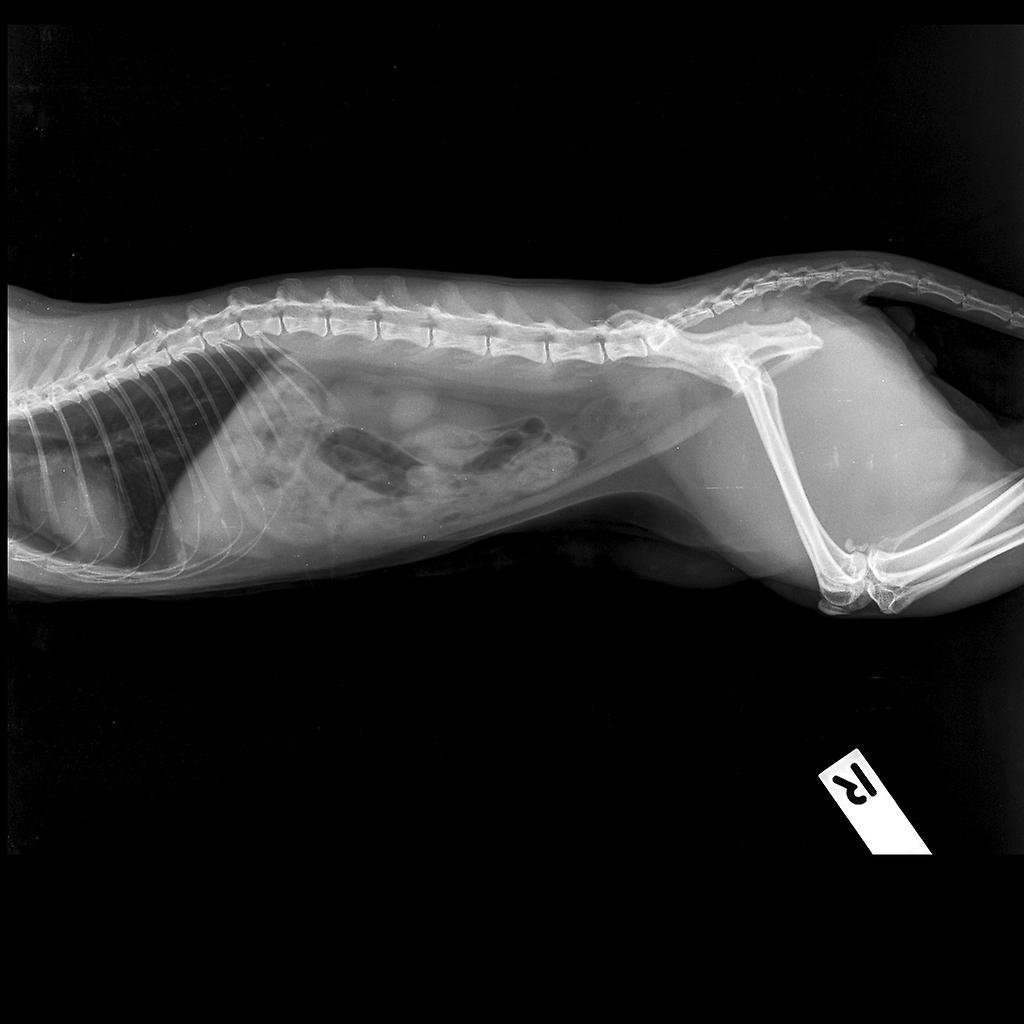

จากการตรวจเลือดทั่วไป พบว่าค่าเลือดปกติ จากการ X-ray พบว่ามีแก๊สสะสมในทางเดินอาหารเล็กน้อย จึงทำการส่งตรวจวินิจฉัยเพิ่มเติมด้วยการ Ultrasound พบว่า กระเพาะอาหารมีการขยายตัวเล็กน้อย ลำไส้เล็กยังไม่พบว่ามีการอุดตัน จึงทำการรักษาด้วยการให้ยาฉีดเพื่อลดการอาเจียน ยาปฏิชีวนะ และให้ยาระบายกลับบ้านไปกินด้วย หลังจากนั้นนัดมาฉีดยาต่อเนื่อง 3 วัน เจ้าของแจ้งว่า น้องไม่มีอาการอาเจียนแล้ว ทานอาหารได้ และในวันที่ 3 น้องก็ถ่ายออกมาเป็นอุจจาระที่มีก้อนขนปนอยู่ด้วยจริงๆ